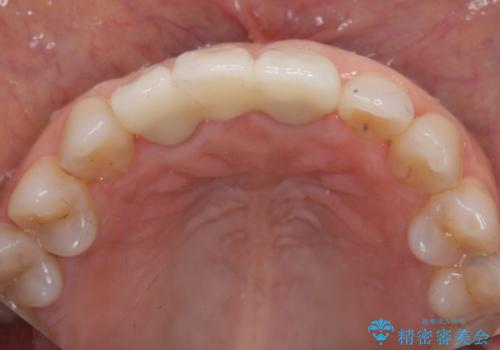

根管治療を行ったのち、歯周外科を行うことで、欠損部の歯ぐきの厚みを出し、縁上歯質を獲得することで、長期的な予後の見込めるブリッジを製作できる環境を整備していきます。

歯周外科をおこなったことで歯ぐきのラインを整え、脱離しないような前歯のブリッジを作製することができました。